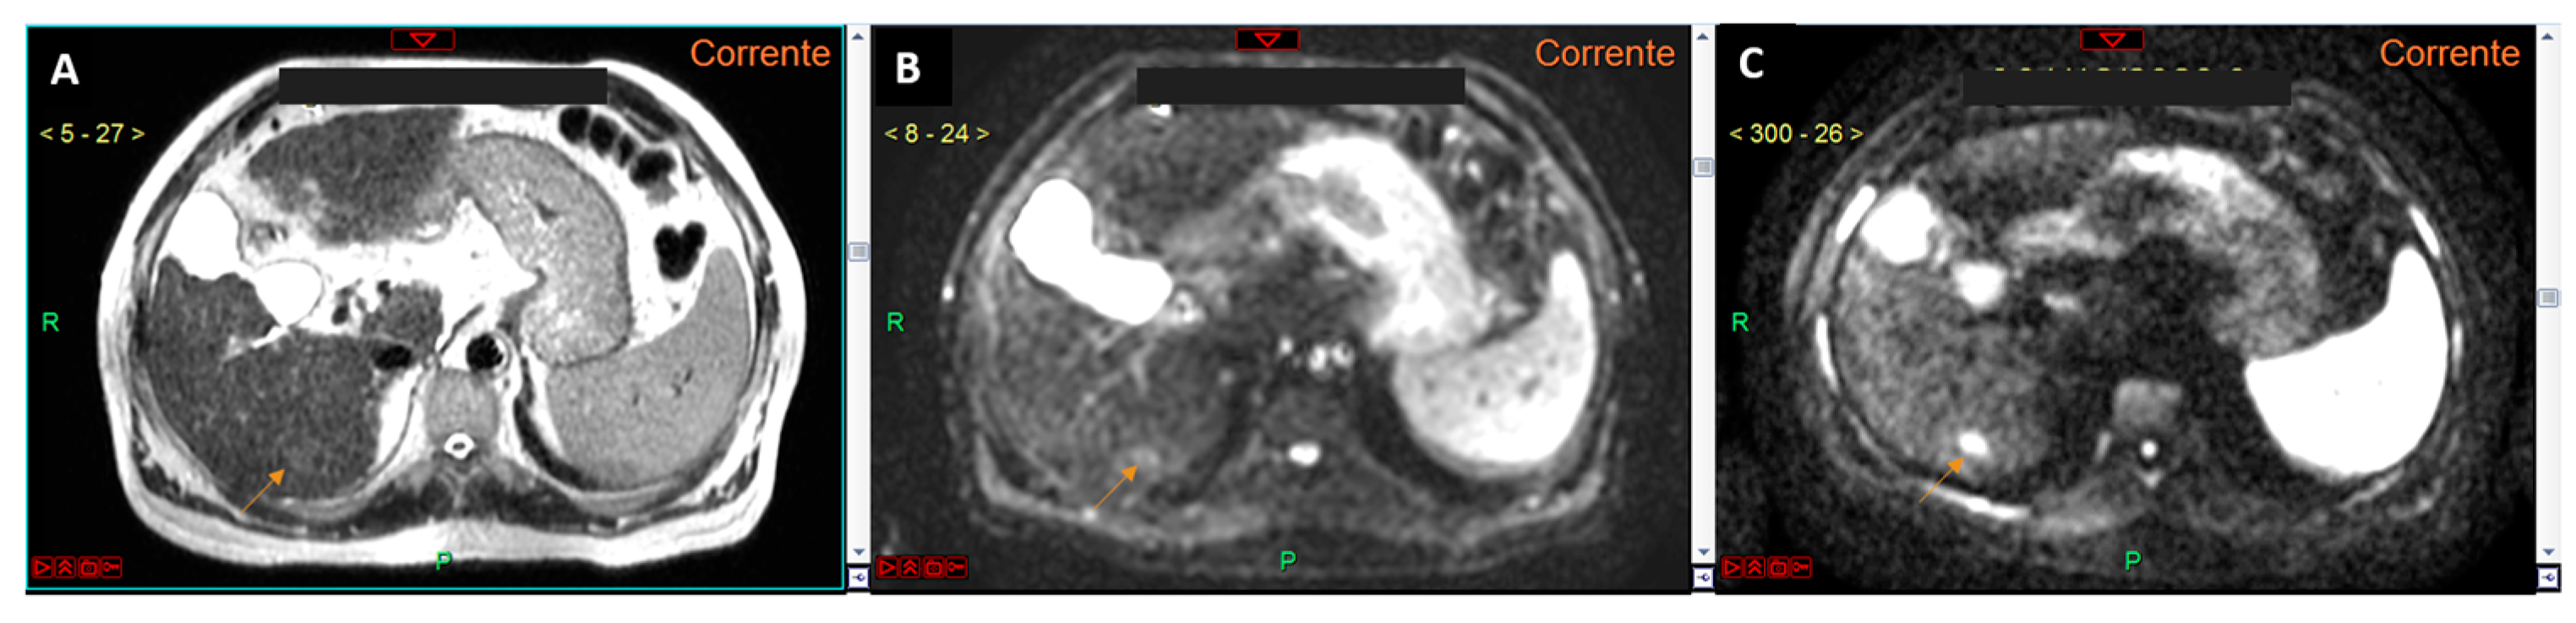

Figure 3.

T2-weighted image (A), diffusion-weighted image with a b-value 0 (B), and diffusion-weighted image with a b-value 800 (C). The lesion located in the liver segment VI is clearly visible (arrows in (A–C)). It is evident that the conspicuity (hyperintensity) of the lesion is greater in the b-value 800 image (C). Moreover, the hyperintensity of the lesion in the b-value 0 image (B) is more pronounced compared to the T2-weighted image (A), confirming our hypothesis that the use of the b-value 0 could replace the T2-weighted sequence in aMRI protocols.